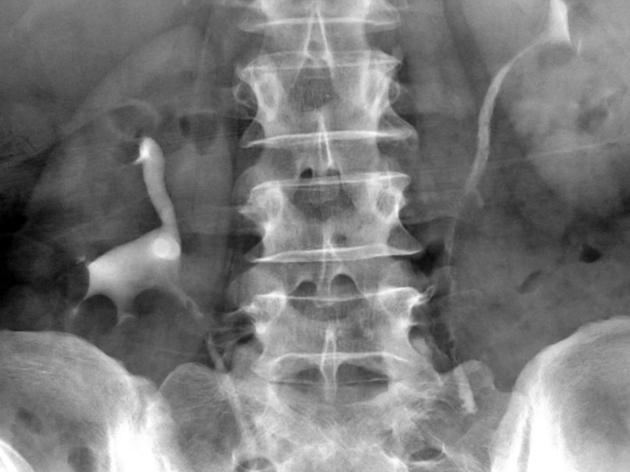

Viêm niệu quản dạng nang (Ureteritis cystica)

Giả túi thừa niệu quản (Ureteral pseudodiverticulosis)